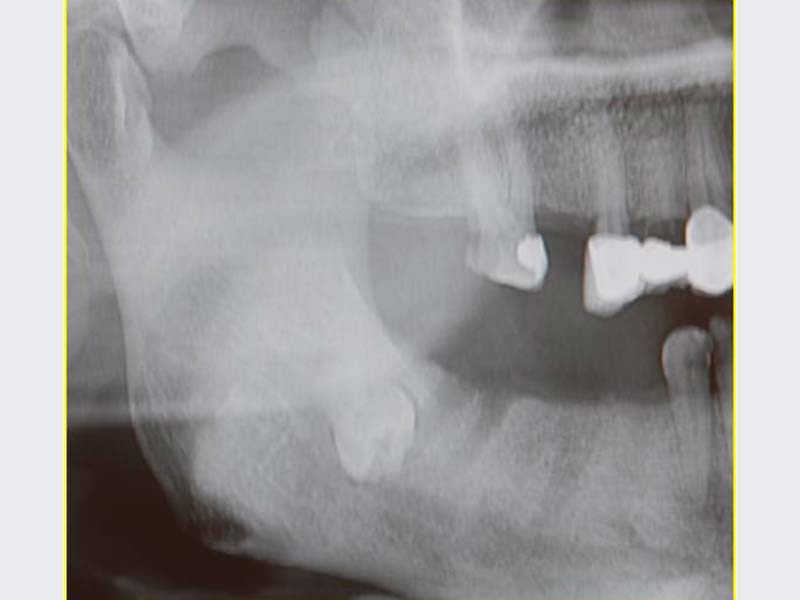

齒源性細菌感染治療

• 齒源性細菌感染治療